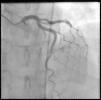

Coronary angiography (Figures 1 and 2) was performed 12 hours after his presentation and showed normal coronary arteries. Left ventriculography (Figure 3) revealed mild posterobasal hypokinesis. Left ventricular ejection fraction was mildly decreased.

Our patient presented to the ED complaining of chest pain associated with elevated cardiac biomarkers four hours after taking eletriptan. He was diagnosed with normal coronary arteries by coronary angiography 12 hours after admission. We believe this case implies a causal association between eletriptan and myocardial infarction, considering the timing of both drug intake and symptom onset. It is important to recall that the maximum recommended single dose of eletriptan is 40 mg or 80 mg in a 24-hour period, so our patient clearly overdosed on this drug.